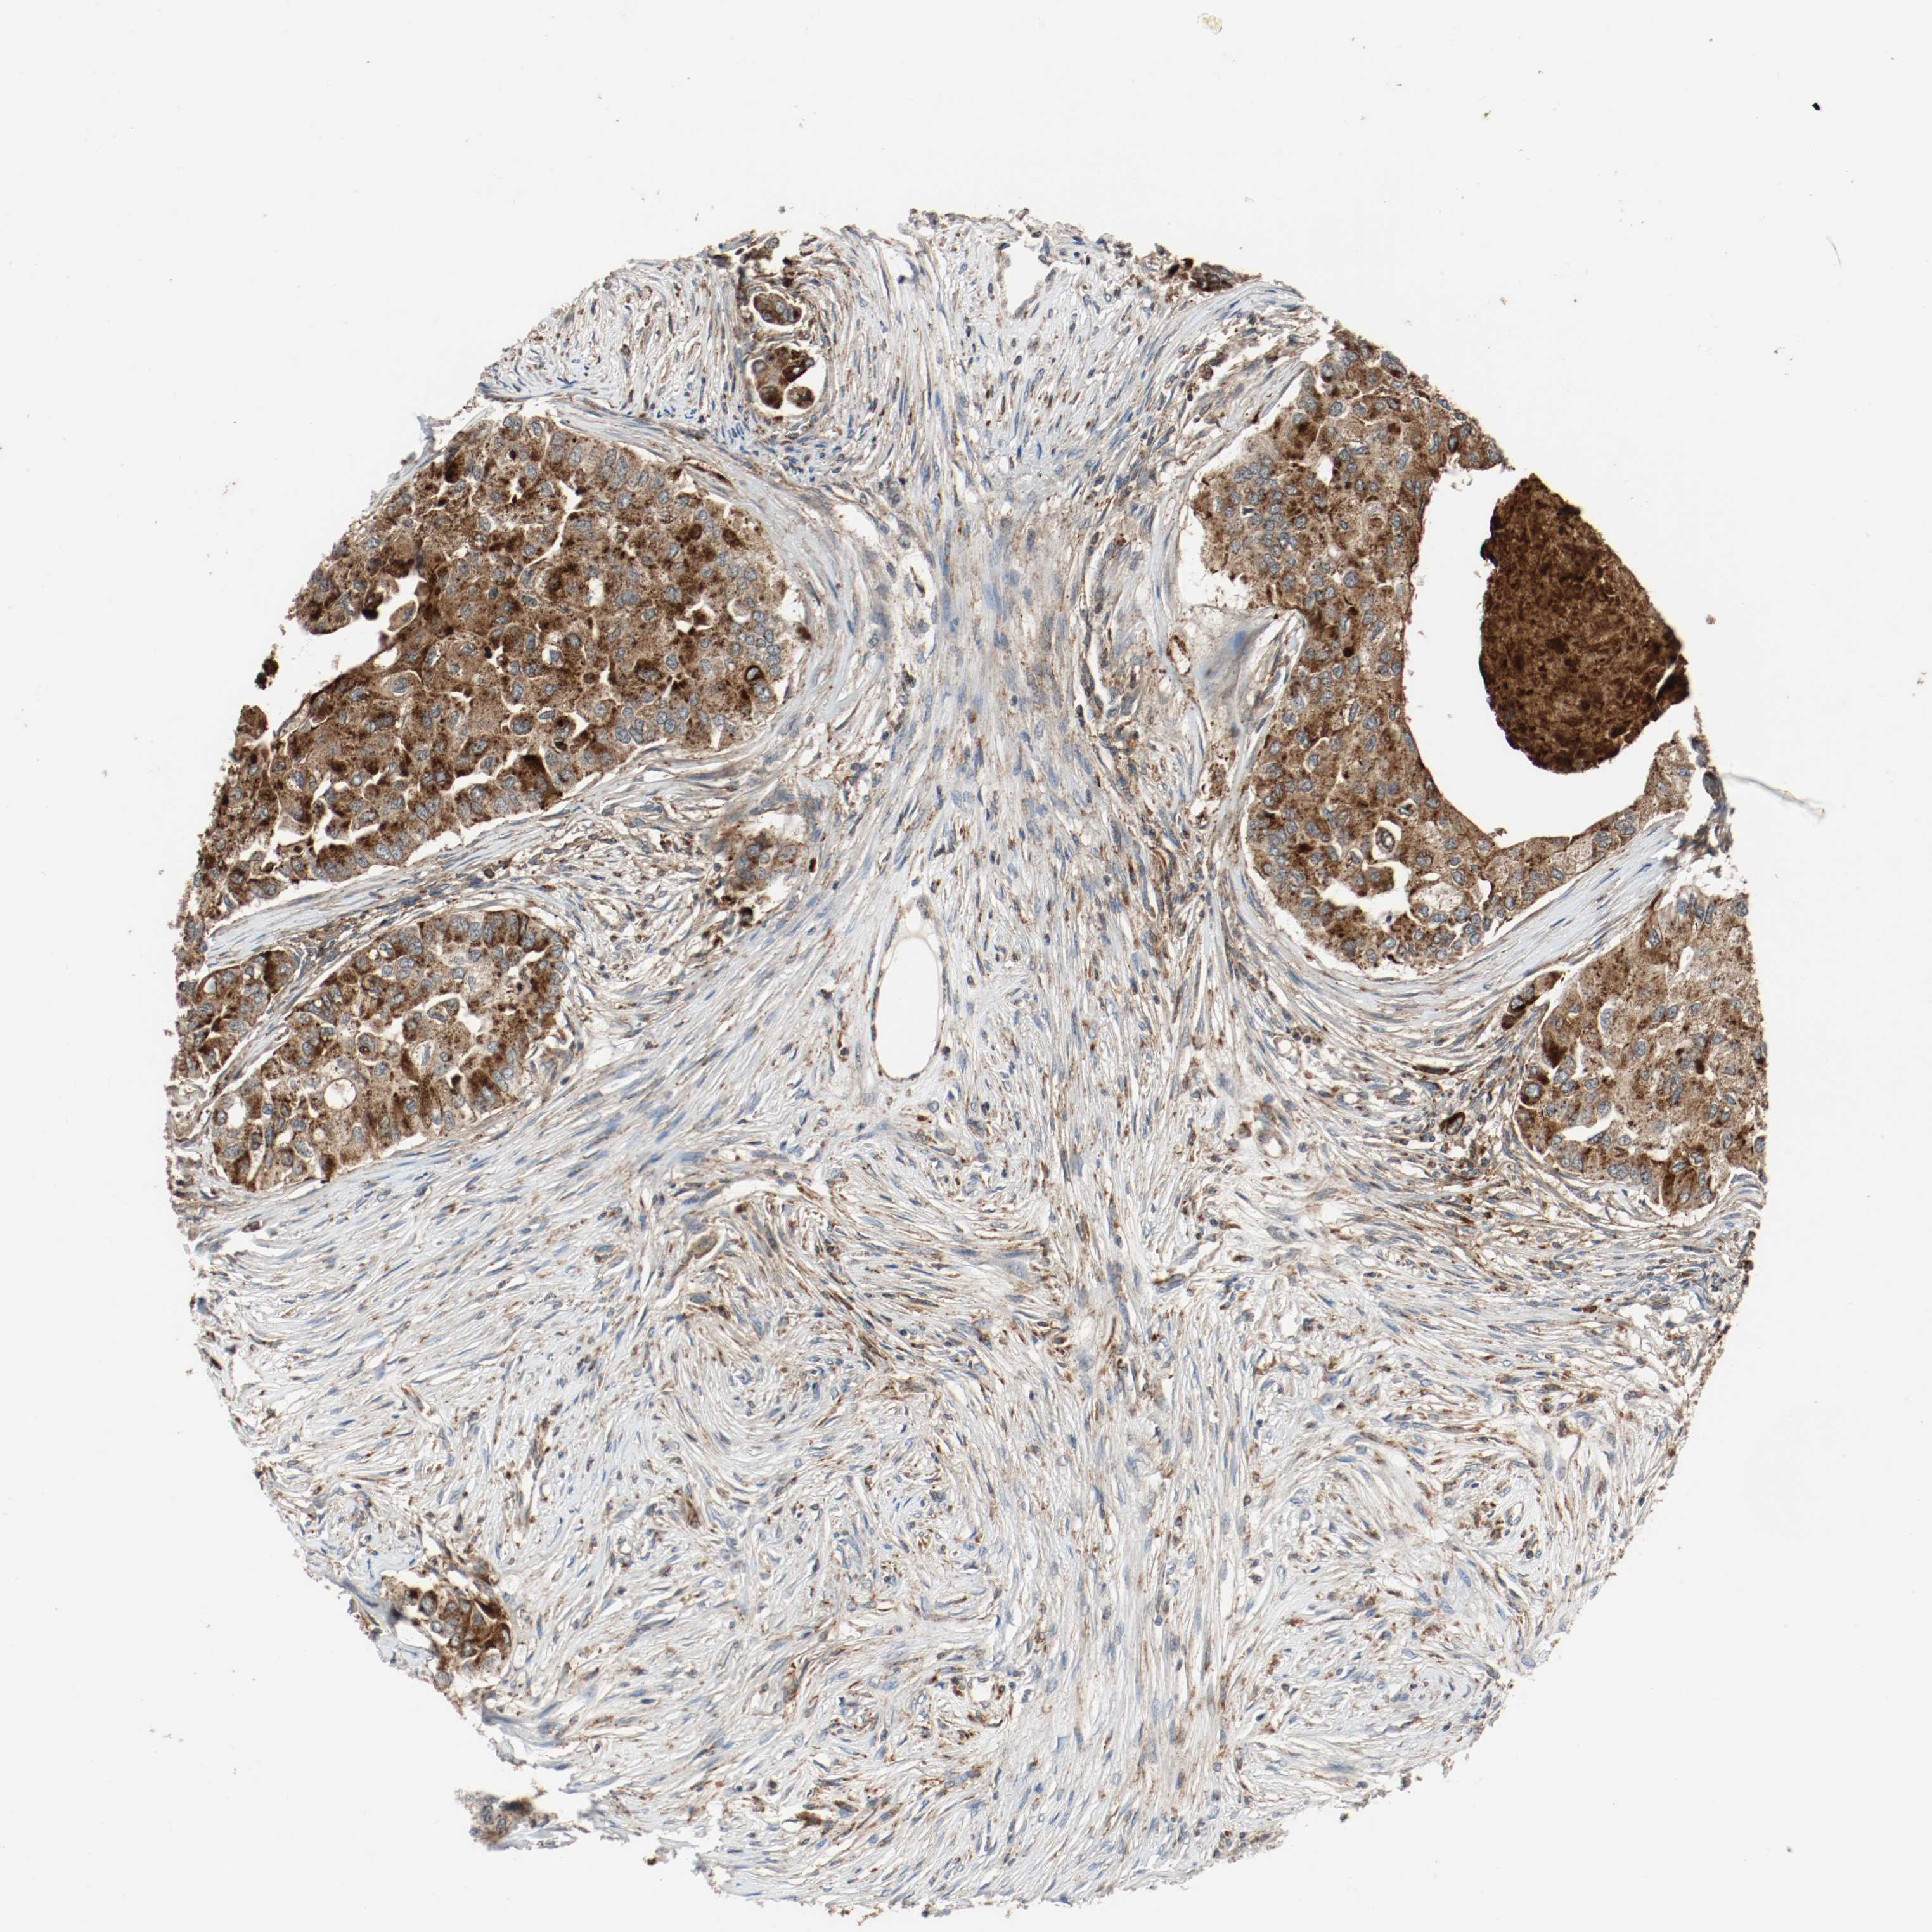

CANCER BREAST CANCER Show tissue menu

BRCA TCGA BRCA VALIDATION PROTEIN EXPRESSION

ANTIBODIES

AND

VALIDATION